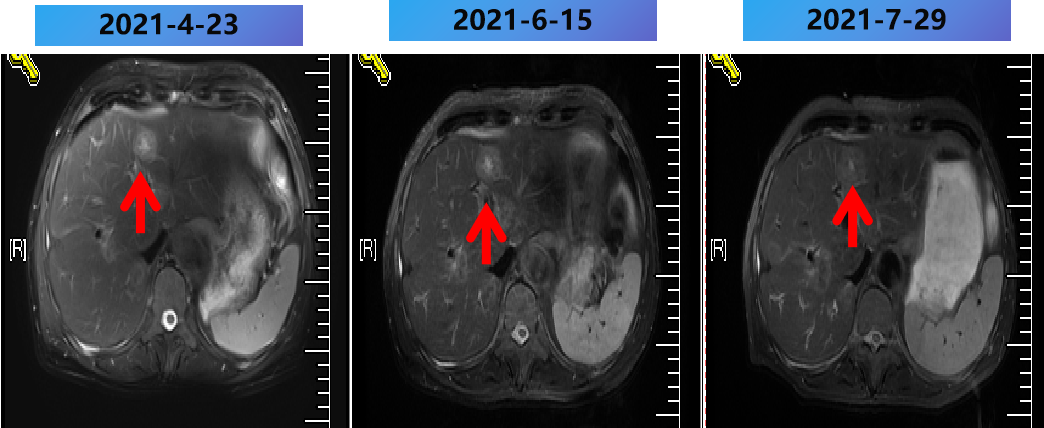

2021-2-20 (术后8m) 当地复查腹部MRI:肝脏多发转移瘤消融术后,较2021-1-5病变数目增多,体积增大。

2021-2-25至2021-7-15 更换方案为bev+伊立替康+雷替曲塞 9周期,部分病灶稳定(SD)。

2021-2-25至2021-7-25 更换方案为bev+伊立替康+雷替曲塞 9周期,部分病灶PD。